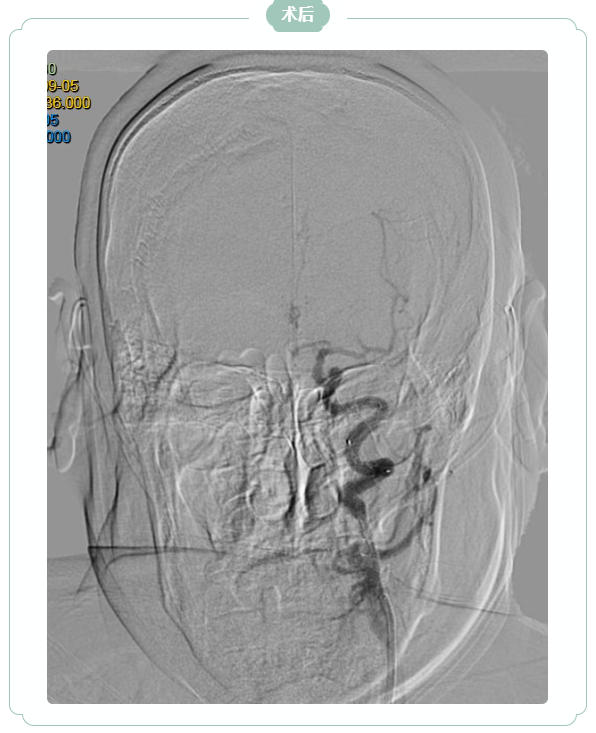

九旬老人“脑动脉迂曲”再挑战

支架植入重燃生活希望

九旬的韩大爷因“言语不利、右侧肢体无力5小时”急诊入院,脑核磁显示左侧大脑半球大面积新发脑梗死,左侧颈内动脉急性闭塞。王振兴主任团队仔细研判影像发现:尽管梗死面积大,但缺血区域内仍有大量“可挽救的脑组织”——若能快速开通血管,韩大爷极有可能恢复独立生活能力。

家属透露,韩大爷2年前曾因左侧颈内动脉重度狭窄就诊于北京某医院,因血管走行极度迂曲、当时手术材料限制,未能成功植入支架。此次急性闭塞正是在“慢性狭窄基础上,因诱因导致急性闭塞”,缺血脑组织尚未完全坏死,但症状仍在持续加重。手术团队再次面临考验:韩大爷血管迂曲如“九曲十八弯”,基础病多,术中稍有不慎便可能引发致命并发症。

凭借丰富经验与先进介入技术,医生精准操控导管、导丝,克服重重障碍,历经2个多小时成功开通闭塞血管,并顺利植入一枚支架。术后第2天,韩大爷右侧肢体功能显著恢复,经过半个月综合治疗,目前已转入康复阶段,生活自理能力逐步提升。